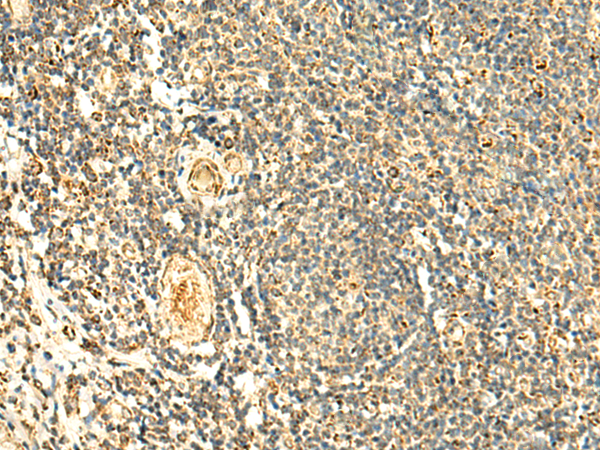

分类: 科研抗体货号: P10087别名: PNAA; PNAD应用: IHC反应种属: Human, Mouse